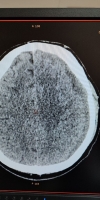

Обследование показало очаги контузии обоих полушарий и небольшого объема гематому слева, которая смещала структуру мозга.

Медики успешно выполнила эндоваскулярную эмболизацию средней оболочечной артерии слева микрочастицами. Уже через 4 суток исследование показало значительное уменьшение гематомы - на 20%, а смещение мозга уменьшилось вдвое.